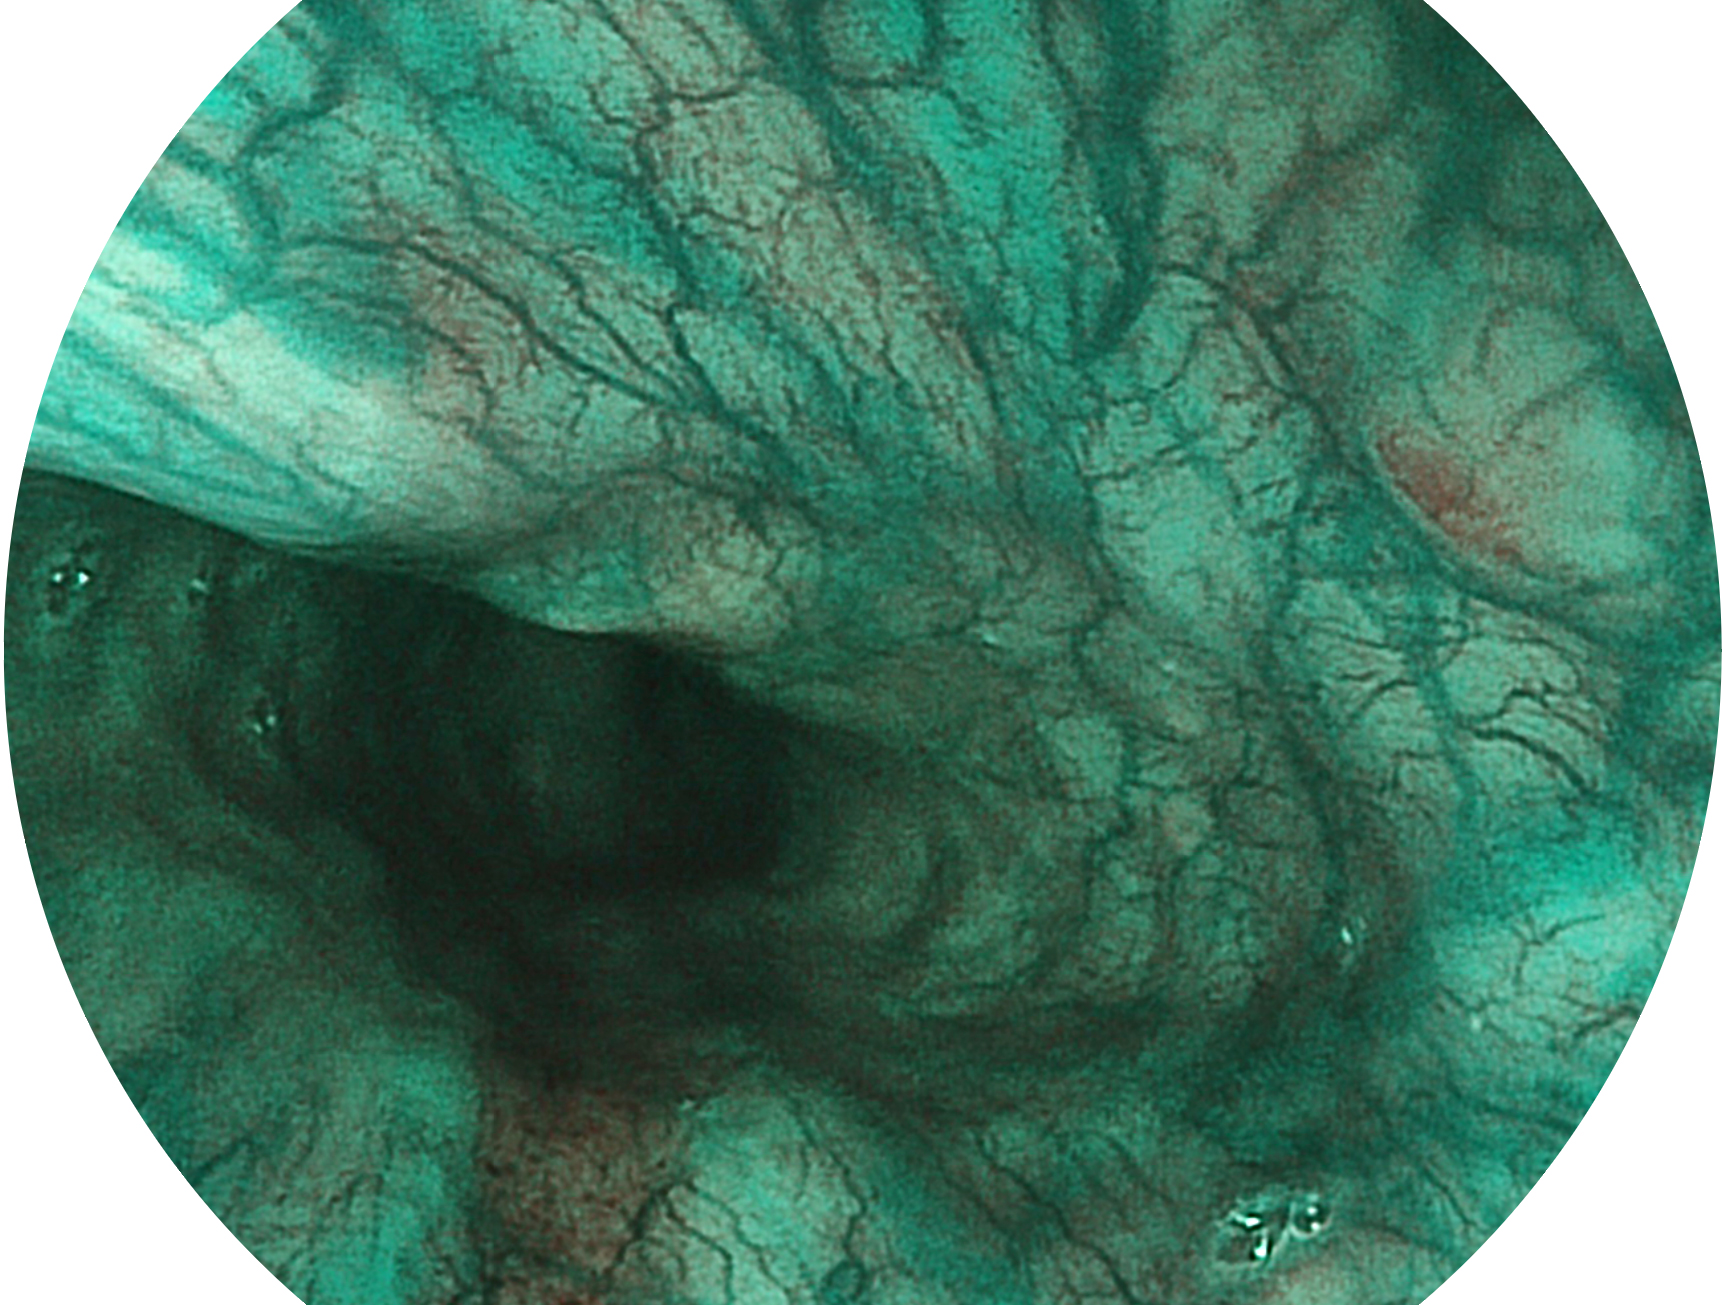

開(kāi)立新開(kāi)發(fā)的內(nèi)鏡染色技術(shù),主要是基于多波長(zhǎng)LED 光源的開(kāi)發(fā),VLS-55Q 四波長(zhǎng)LED 光源是由四個(gè)不同顏色的LED光按照相應(yīng)照明模式所規(guī)定的特定發(fā)光比例進(jìn)行合束后形成,合束后形成的照明光的光譜由紅光、綠光、藍(lán)光及藍(lán)紫光這四個(gè)不同的波段范圍構(gòu)成。具有更高光譜自由度,通過(guò)光譜比例的控制,實(shí)現(xiàn)了聚譜成像技術(shù),英文全稱為“Spectral Focused Imaging, SFI”,縮寫為“SFI”和光電復(fù)合染色成像技術(shù),英文全稱為“Versatile Intelligent Staining Technology, VIST”,縮寫為“VIST”。